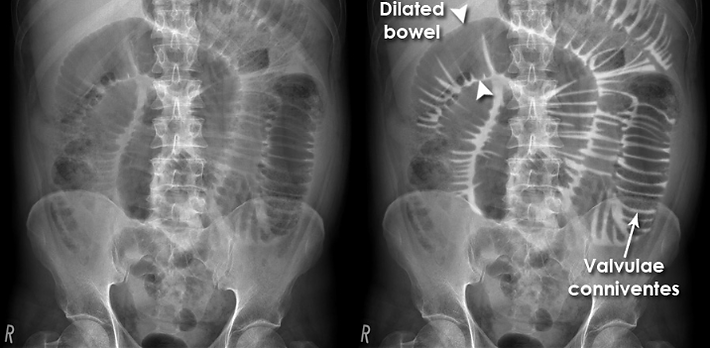

Small bowel: mostly central, with valvulae conniventes traversing the full width¹.

Small Bowel Obstruction: multiple dilated central loops, step-ladder pattern, air-fluid levels on erect, and the string-of-pearls sign (gas trapped between folds in fluid-filled loops).1,3,5